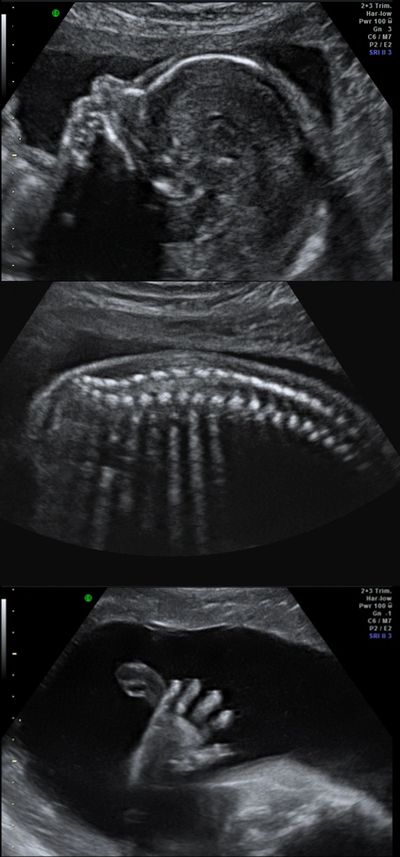

In the year 2011 to 2017 Chennai District Blindness Control Society has received 14271 numbers of cornea through eye bank of Regional Institute of Ophthalmology and Government Ophthalmic Hospital Chennai and through NGOs and they were used in cornea transplantation totally 6767 persons were benefited through this programme. 4D Ultrasound Facial Expressions of a fetus. Because the mitral valve is the gate between the two left heart chambers it leaks blood and the heart enlarges.

Best Anomaly Scan In Chennai Anomaly Scan Cost In Chennai Mid Pregnancy Scan In Chennai Gynecologist In Mandaveli Chennai Fertility Hospital In Chennai Ivf Treatment In

Fetal Growth Scan Chennai Growth Scan In Pregnancy Procedure Report Cost

Anomaly Scan In Chennai Anomaly Scan In Anna Nagar Anomaly Scan Near Me Anomaly Scan Price Anomaly Scan In Golden Scans Tiffa Scan In Chennai Tiffa Scan In Anna Nagar Tiffa Scan

Fetal Anomaly Scan Pregnancy Scan Types Of Anomaly Scan Apollo Cradle

Anomaly Scan In Chennai Anomaly Scan Procedure Report Details